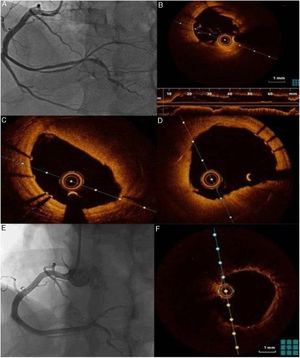

No 1° dia de internamento, o doente fez paragem cárdiorrespiratória em assistolia precedida de bradicardia grave, recuperada no fim de dois ciclos de suporte avançado de vida, tendo‐se optado pela colocação de sistema pacemaker provisório e nova angiografia coronária. Dada a instabilidade hemodinâmica e elétrica optou‐se, após nova coronariografia com apoio de imagem por IVUS – que após confirmar a presença do fio guia no verdadeiro lúmen mostrou aparente progressão da disseção da DA para o 1/3 proximal – pela angioplastia da descendente anterior com colocação de scaffold Absorb® 3.50mm/23mm no segmento proximal e sobredilatação com balão NC 4,0mm/20mm, mantendo o vaso distal fluxo TIMI 2 (Figura 4). O ecocardiograma realizado ainda no primeiro dia mostrou uma função sistólica global moderadamente diminuída – FEVE ∼45% com o ápex e segmentos apicais acinéticos e hipocinésia do segmento médio do SIV e da parede anterior. No terceiro dia de internamento, por não apresentar novos episódios de instabilidade elétrica, retirou‐se o pacemaker provisório. Apesar da estabilidade hemodinâmica, elétrica e clínica, analiticamente não apresentou uma diminuição sustentada dos marcadores de necrose miocardíaca, apresentando oscilações durante o internamento, pelo que ao sexto dia de internamento, após discussão multisdisciplinar, optou‐se pela angioplastia do segmento médio e distal com pré‐dilatação com balão 2,5/30mm, seguido de colocação de dois scaffolds Absorb® 3mm/28mm e 2,5mm/23mm. Tratando‐se de uma zona de bridging, implantou‐se um stent com fármaco mais distal (Xience Alpine® 2,5mm/38mm) em overlap com os scaffolds com bom resultado final (Figura 4).

A: Passagem de guia floppy até DA distal B e C: implantação de scaffold Absorb 3,50mm/23mm. D e E: Imagem de IVUS após implantação de scaffold Absorb mostrando scaffold bem aposto e expandido, selando a entrada proximal da disseção F: Implantação em D6 de internamento de dois scaffold Absorb 3mm/28mm e 2,5mm/23mm e de um stent com fármaco (Xience Alpine 2.5mm/38mm) com bom resultado angiográfico final.